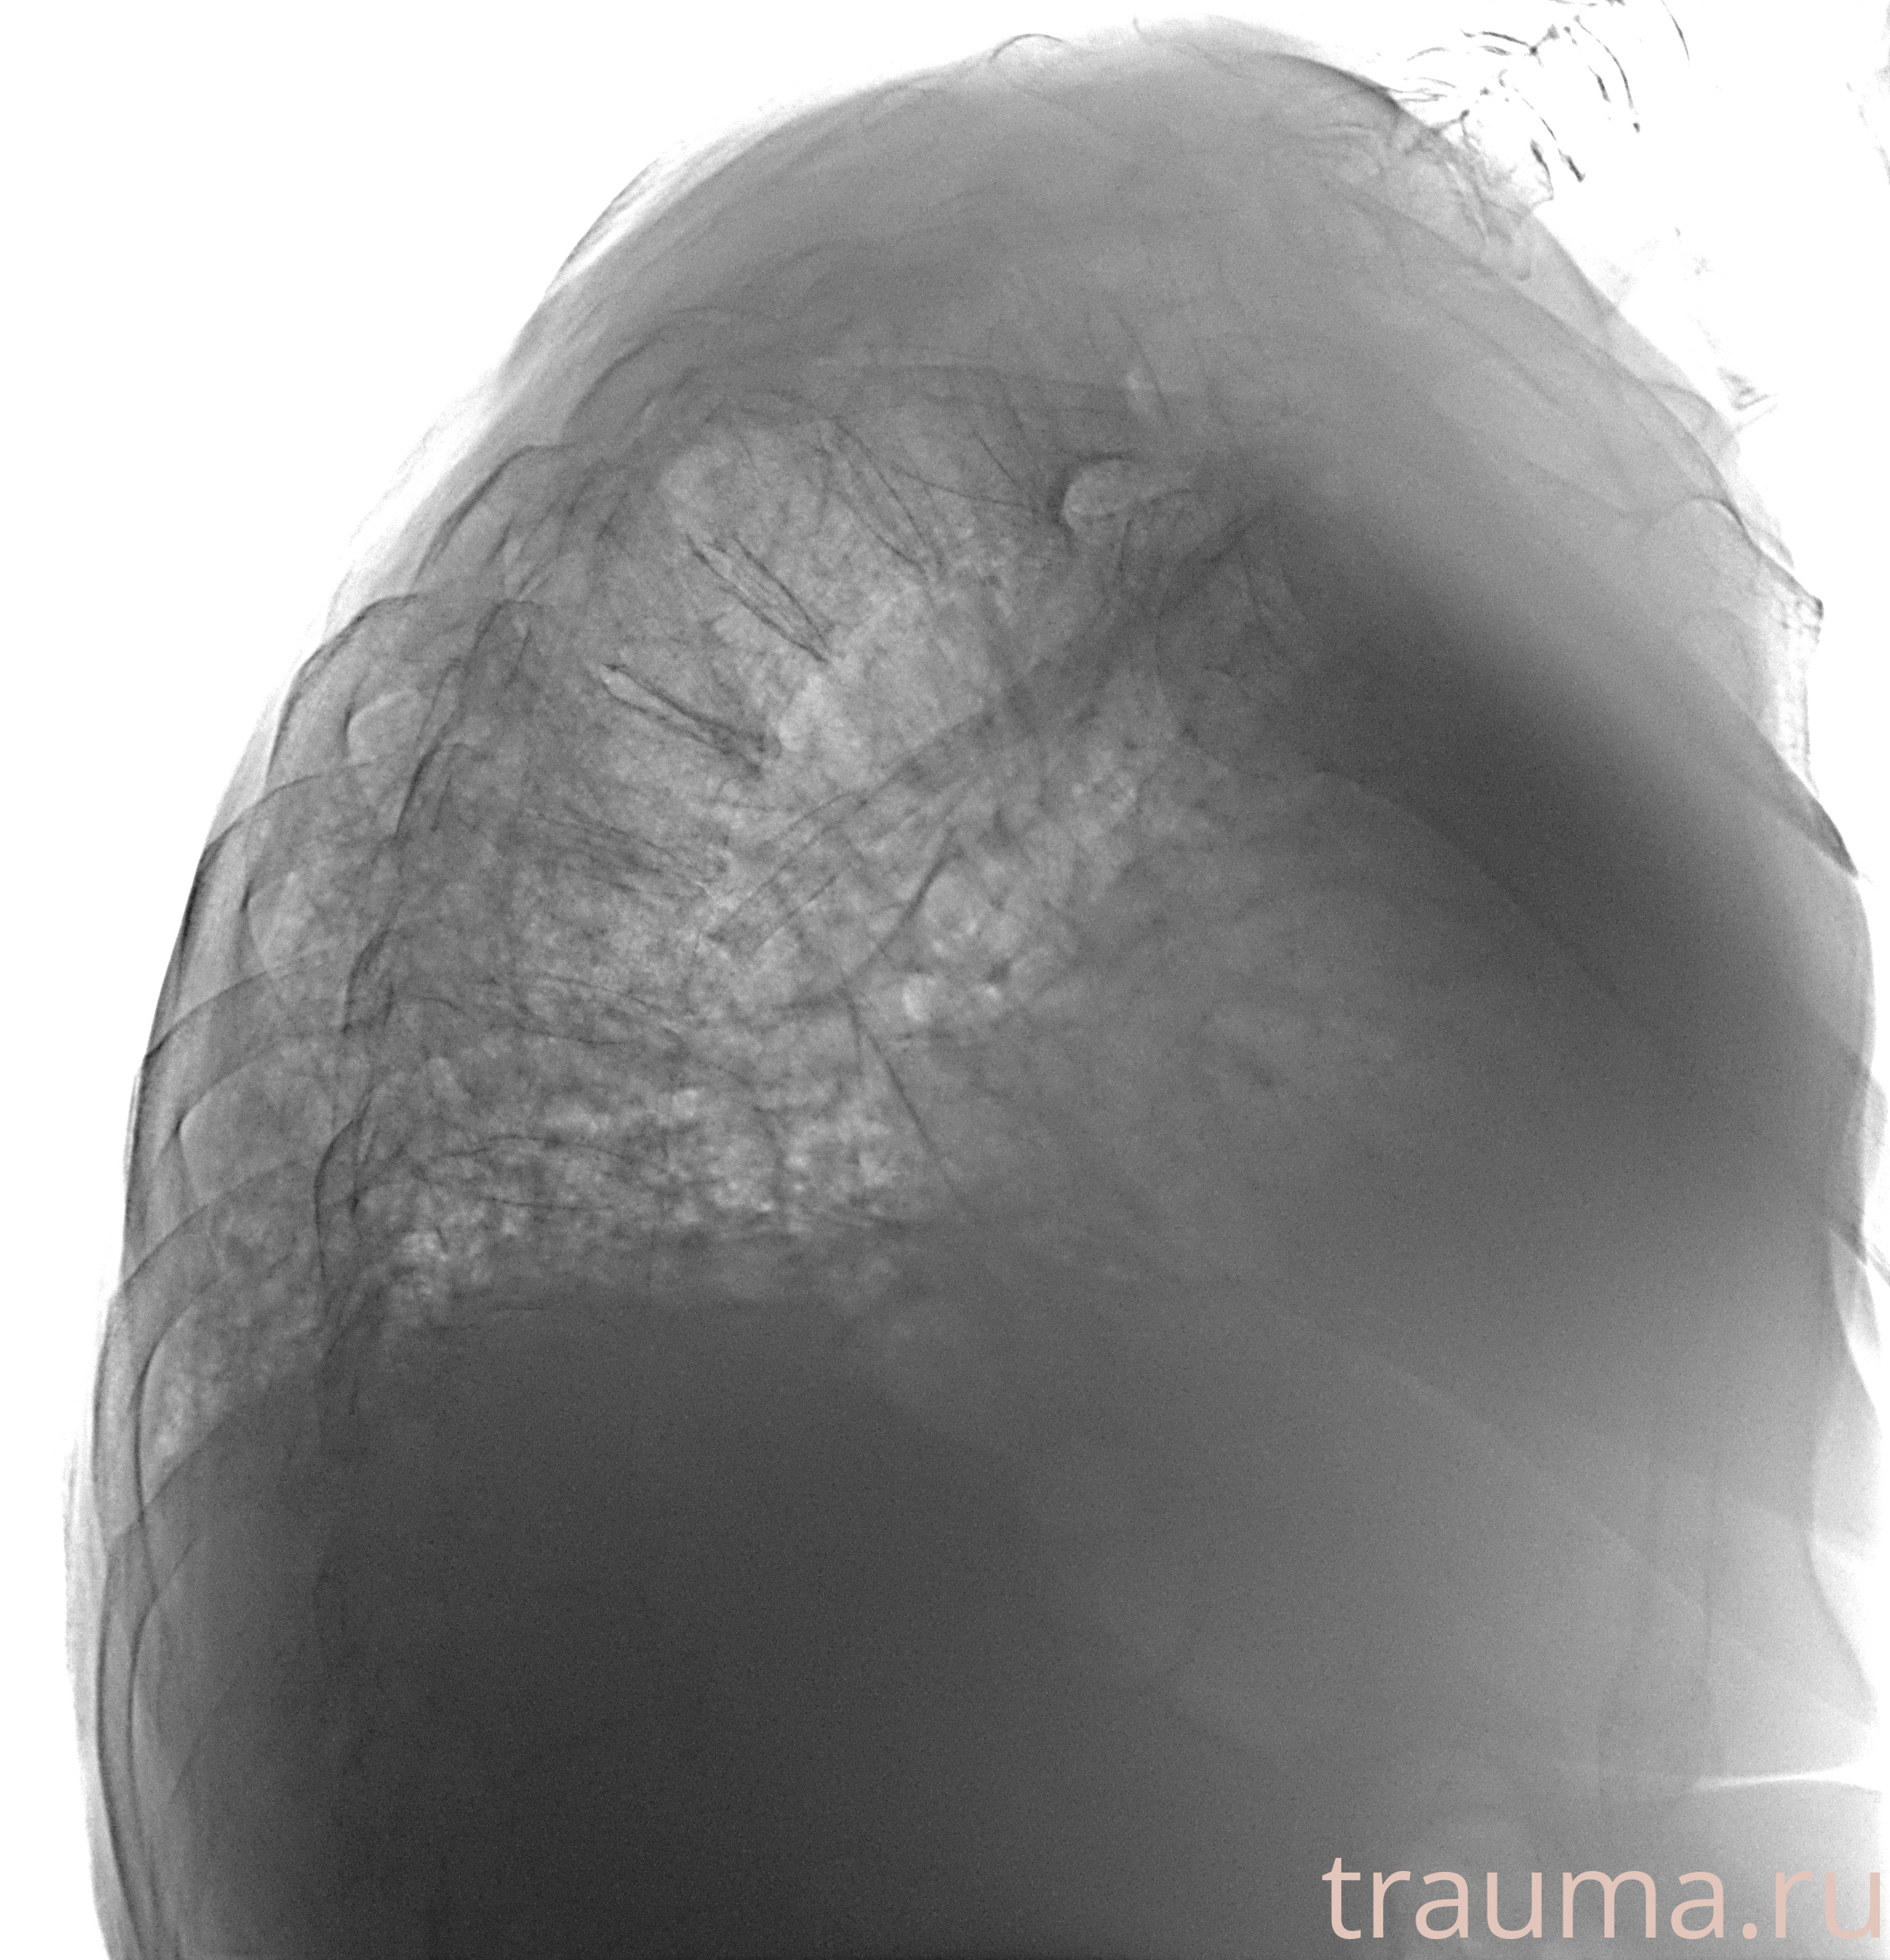

Рентген на дому: по вашему адресу приезжает врач-рентгенолог, травматолог-ортопед с мобильным рентгеновским аппаратом, проводит диагностику травмы или заболевания, делает необходимые рентгенограммы, дает рекомендации по дальнейшему лечению. Получить качественные снимки в домашних условиях возможно благодаря уникальной методике, разработанной МосРентген Центром для института  Склифосовского

при переломе шейки бедра и пневмонии от компании МосРентген Центр - партнера Института имени Склифосовского